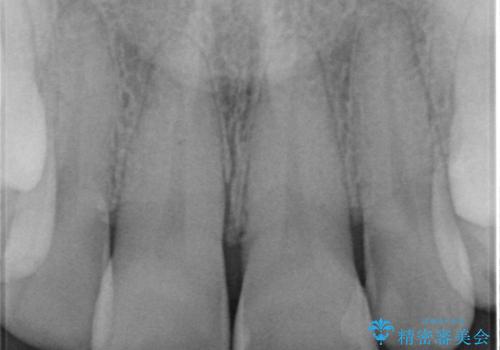

虫歯になっている歯はないので、患者様としっかり相談をして被せ物治療をする事に致しました。

適合の良い被せ物が入りました。

樹脂の素材とは違い、セラミックやジルコニアの素材の被せ物は劣化をしません。また、虫歯の再発リスクも低くなります。